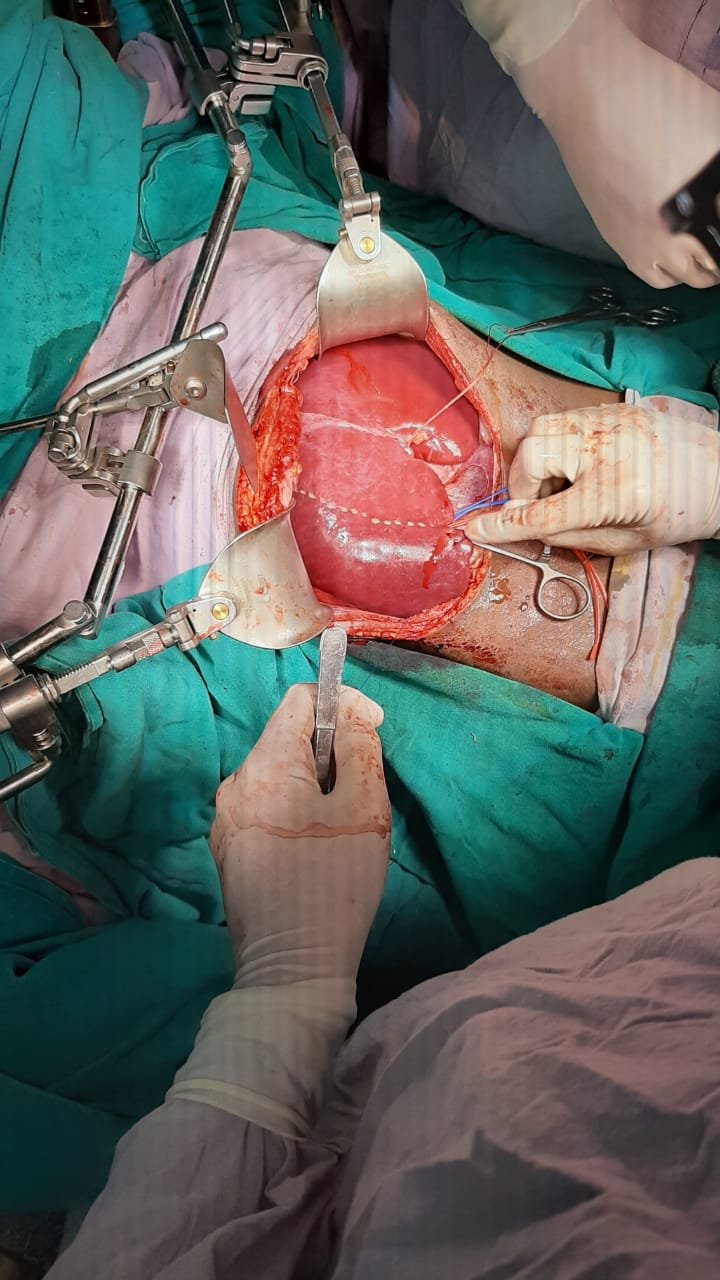

Liver Surgery performed was right hepatectomy for hepatoblastoma in seg 6,7 and 8 of liver; in 11 year old girl in SMS Hospital, Jaipur